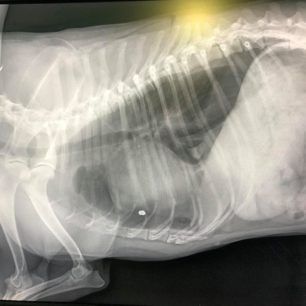

Στην κτηνιατρική κλινική του Νίκου Γαρμπή στην Καλλιθέα της Αττικής νοσηλεύεται σε κρίσιμη κατάσταση ο σκύλος που ξημερώματα εντοπίστηκε να βαριανασαίνει στην αυλή του σπιτιού του στον Πειραιά στη διασταύρωση των οδών Γυθείου και Αιγάλεω. Όπως έδειξε η ακτινογραφία το ζώο πυροβολήθηκε με αεροβόλο και το σφαιρίδιο πέτυχε τον σκύλο στον θώρακα, ανάμεσα στον πνεύμονα και την καρδιά.